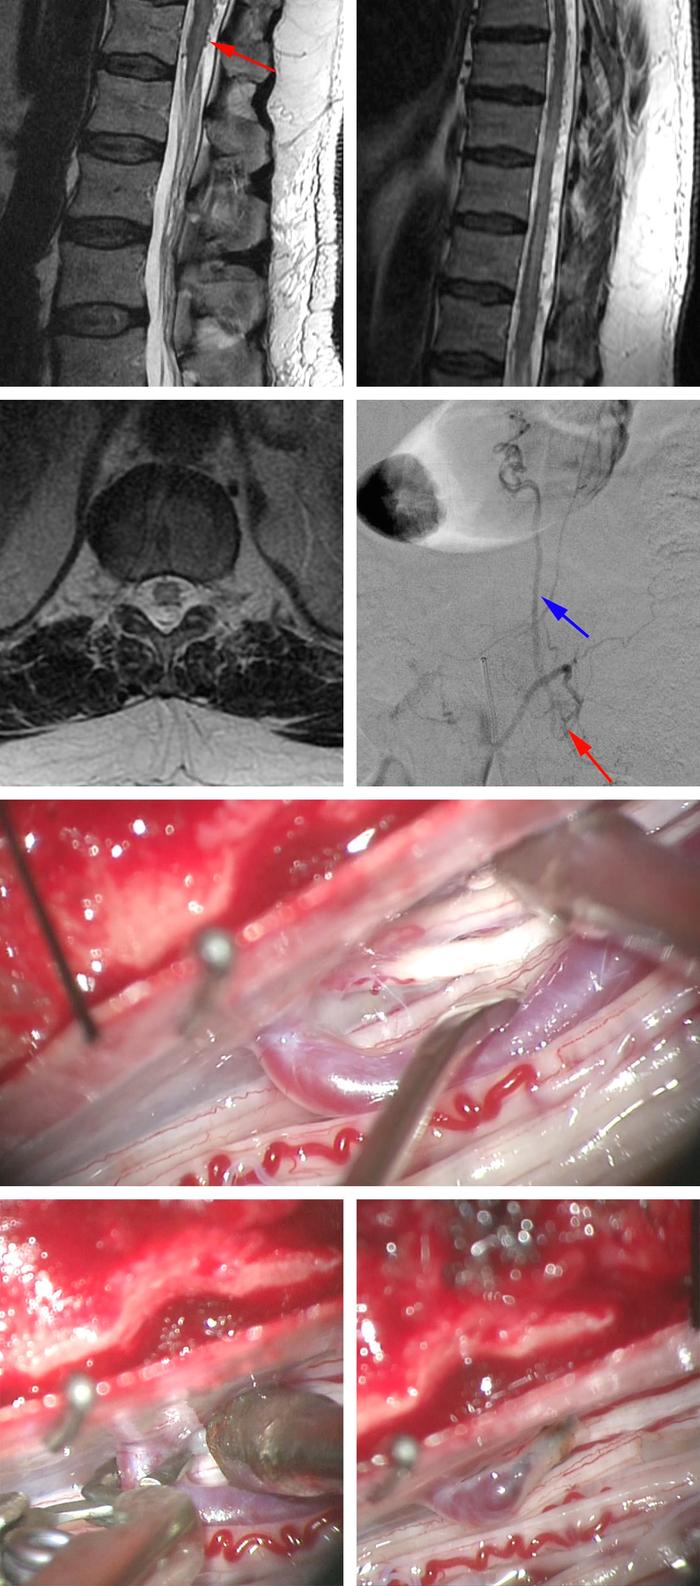

3:图中磁共振所示图片来自一名表现为一过性下肢轻瘫症状的52岁男性。首次MRI检查除马尾部位血管扩张外未发现其它明显异常(左侧最上图,箭头)。胸部磁共振显示出硬膜内脊髓背侧血管增多(右上图)。脊髓血管造影显示L1脊膜动静脉瘘并脊髓背侧扩张的动脉化静脉(第二排;红色箭头指示瘘口,蓝色箭头指示脊髓背侧动脉化的静脉)。术中探查发现瘘口引流静脉位于脊髓背侧L1神经根入口处(第三排;神经根入口处位于吸引头尖端)。术中先行临时阻断夹阻断瘘口,双极电凝处理瘘口处引流静脉,断开动静脉间异常交通(底图),然后去除临时阻断夹,硬膜水密缝合。